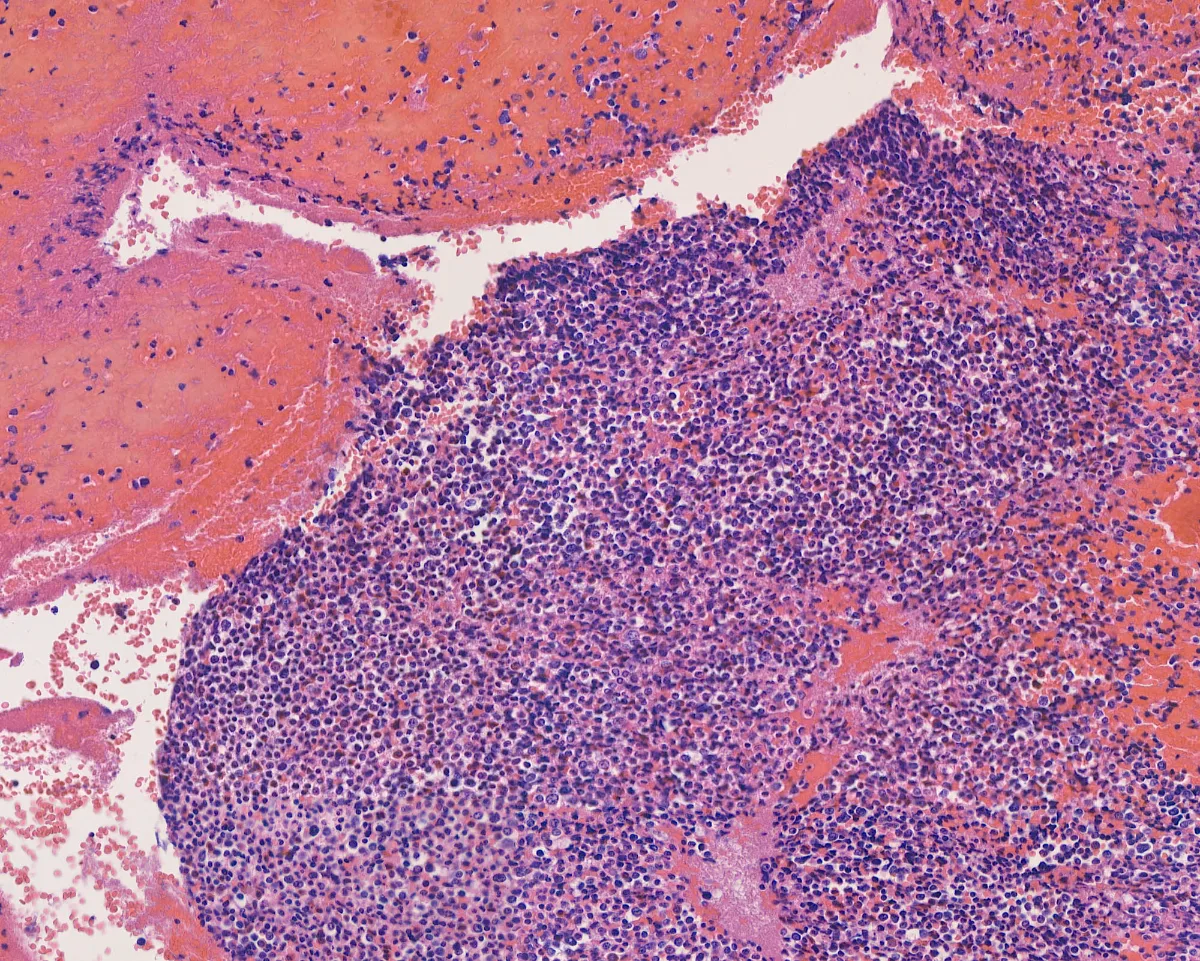

Imágenes:

Hematoxilina-eosina 2

- Está compuesto por sábanas de células de tamaño intermedio de origen mieloide, positivas para CD34 y MPO (PMID: 39328673).